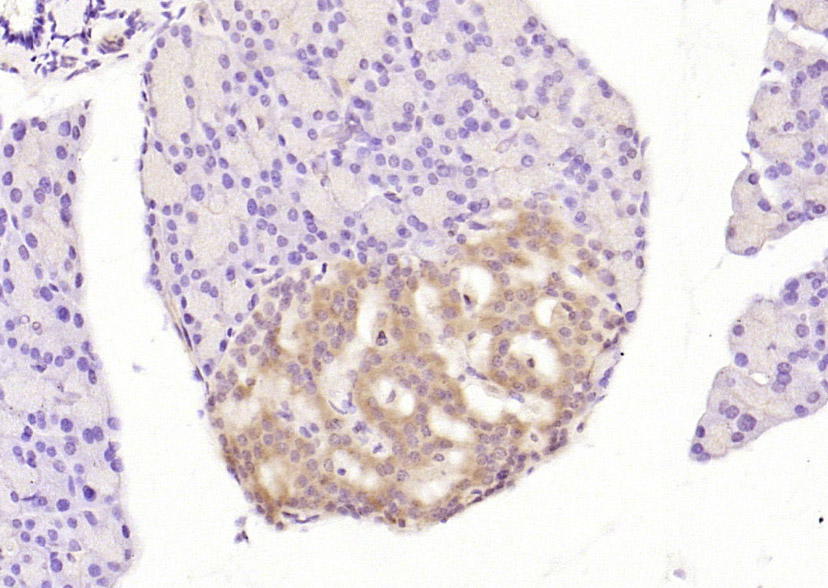

| IHC-P | Human, Mouse, Rat | Rabbit, Pig, Cow, Dog | 1:100-500 |

| IHC-F | Human, Mouse, Rat | Rabbit, Pig, Cow, Dog | 1:100-500 |